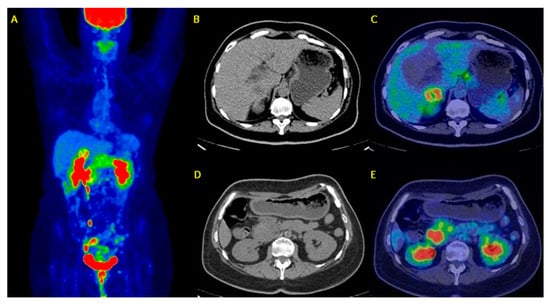

| 18 | Albano et al. [33] | 2018 | Retrospective study | 52 (59 (42–78)) | Restaging 28 surgery, 12 neoadjuvant chemotherapy+surgery+radiotherapy, s6 neoadjuvant chemotherapy+surgery, and 6 chemotherapy | PET/CT has a high diagnostic accuracy in the restaging process and significantly influences the therapeutic management in ∼30% of cases. |